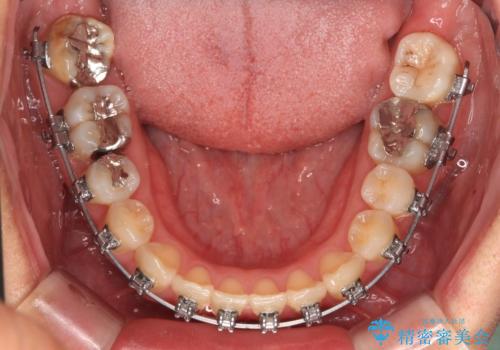

- 矯正装置

- メタルブラケット

ワイヤー矯正でもマウスピース矯正でも可能でしたが、短期間で、自身の手を煩わせることなく治療を行いたいとのことで、ワイヤー装置にて矯正治療を行うこととしました。

舌の突出癖により、治療過程でスペースが多くできましたが、舌のトレーニングを頑張っていただき、1年強で終えることができました。